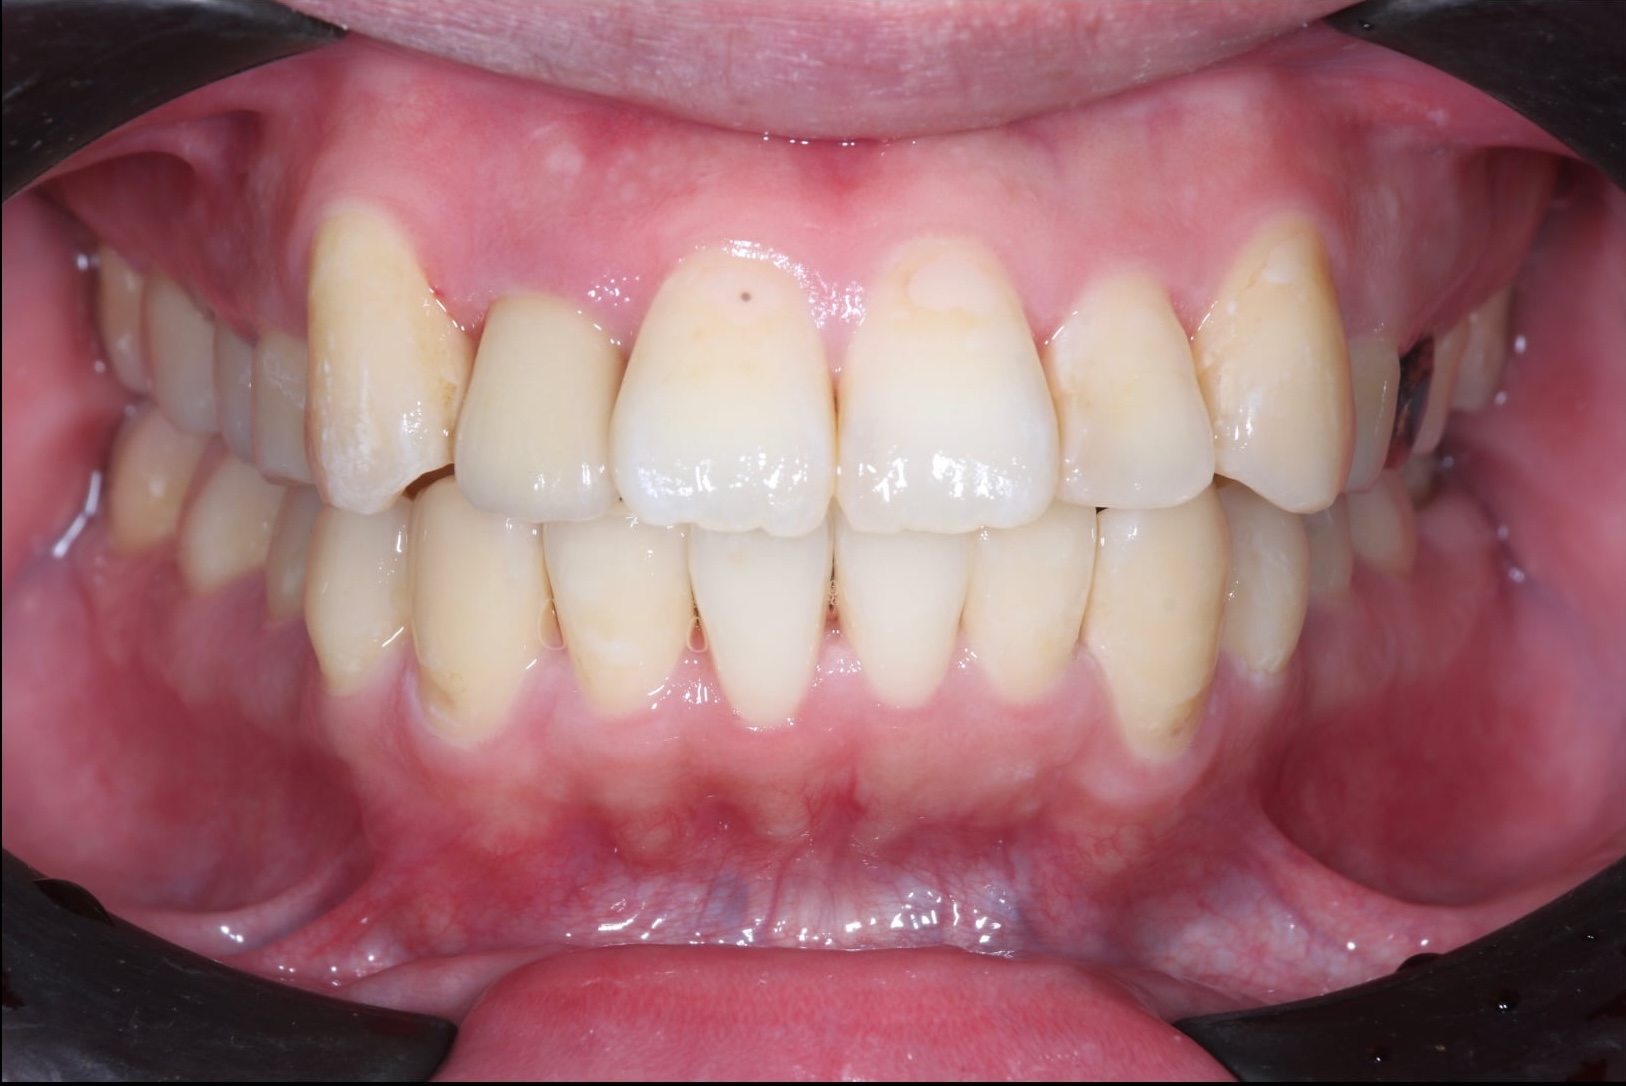

症例3:重度の叢生と開咬を矯正治療で改善した症例

術前の状態

術後の状態

治療概要

| 患者さんの状態 | 重度の叢生と開咬 |

|---|---|

| 治療内容 | MEAWを用いた矯正治療(非抜歯) |

| 治療期間 | 約2年 |

| 治療費用 | 1,320,000円(税込) ※矯正治療費のみです。 |

| 治療のリスク | 歯肉退縮、自由診療、後戻り、口腔内清掃が難しい |